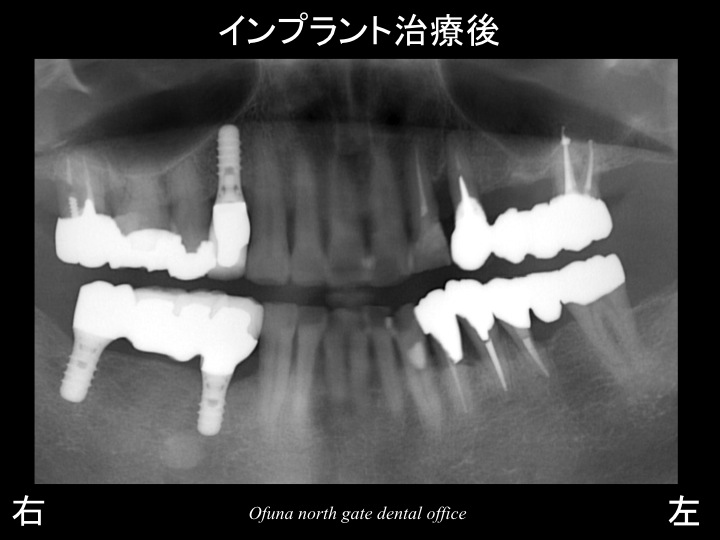

そして、以下がインプラント治療終了後になります。

このように口腔内全体の将来性を考えることにより、

インプラントの治療本数を減らすことが可能になります。